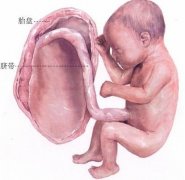

怀孕八个月男胎儿B超图:

当怀孕时间达到八个月的时候,这表明腹中的胎儿已经完全成型了,肌肉和神经都已经很发达。心脏和听觉器官大体已经发育完全。而且活动渐渐增多,这个时候胎儿在腹中的活动越来越明显,甚至你可以看到胎儿踢你肚子,这个时候的胎儿一般来说是都不朝下,这也是孩子出生时候的姿势。8个月胎儿的体重一般是来说随着时间的曾可以可以从1.3公斤慢慢涨到2公斤,体长大约40厘米。

怀孕八个月男胎儿图

到了怀孕八个月的第二周也就是30周的时候胎儿大脑和神经系统已发达到了一定程度。皮下脂肪继续增长。几乎大多数胎儿此时对声音都有了反应。头部还在增大,而且这时大脑发育非常迅速。